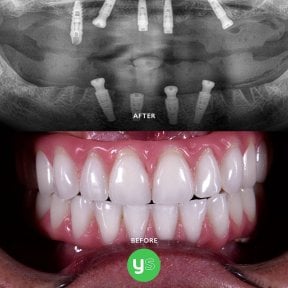

У Мексиці безпечно встановлювати зубні імплантати All-on-4. Багато стоматологічних клініках Мексики працюють кваліфіковані, досвідчені стоматологи і техніки, які встановлюють зубні імплантати All-on-4. Тим не менш, вам потрібно знайти клініку з гарною репутацією, щоб забезпечити найкращу якість обслуговування та результат. Перевірте повноваження клініки, підтвердіть її акредитацію та запитайте у своїх пацієнтів фотографії зубних імплантатів All-on-4 до та після. Крім того, після лікування в Мексиці ви можете відвідати свого стоматолога або ортопеда, щоб переконатися, що все виглядає та функціонує належним чином.